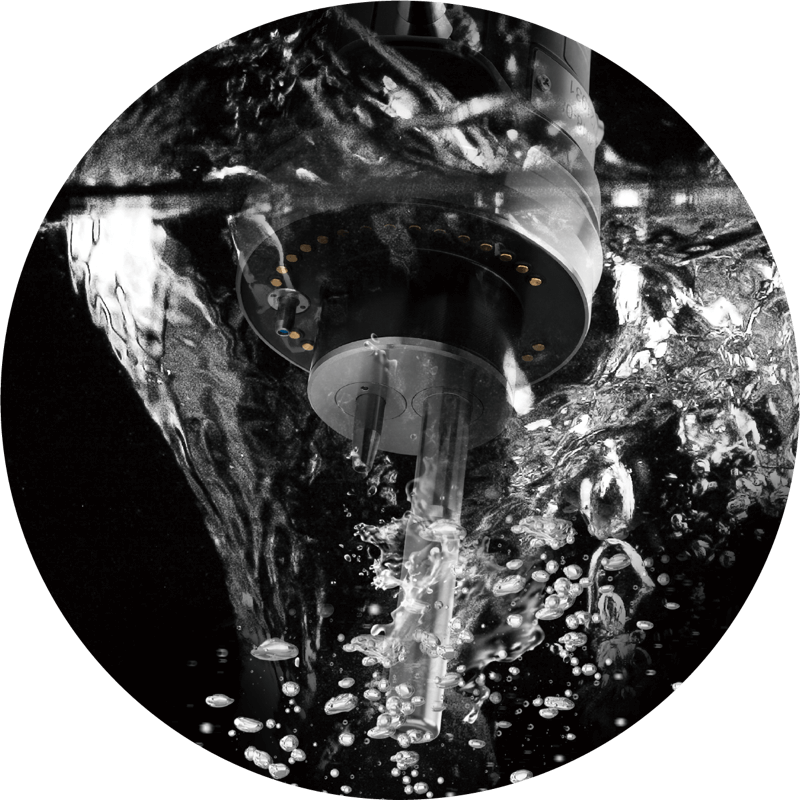

全系标配辅助送水功能,可快速冲洗粘膜表面和粘液及出血,发现病变和出血点。

辅助送水管道: 有

辅助送水管道: 有